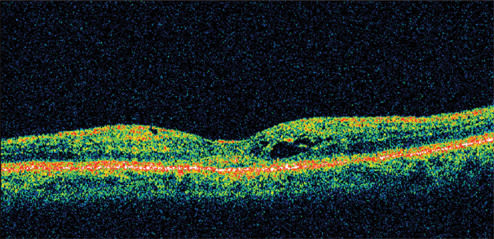

Figure 3. By 12 weeks, the patient's visual acuity had improved to 20/20 with a reduction in retinal thickness of 262 μm from her pretreatment status.

Presenting visual acuity was 20/40. Her IOP was 23 mm Hg and retinal thickness was 478 μm on OCT (Figure 1). She was treated with nepafenac qid for 6 weeks and tapered over the ensuing 6 weeks. Her vision improved to 20/25 by 1 month with significant reduction in her retinal thickness (Figure 2). By 12 weeks, her visual acuity had improved to 20/20 with a retinal thickness of 216 μm and a normal foveal contour. This represents a reduction in retinal thickness of 262 μm from her pretreatment status (Figure 3). However, she continued to report a mild reduction in contrast sensitivity.

Figure 5. One month following treatment with nepafenac, vision improved to 20/32 with a marked reduction in retinal thickness. By 12 weeks, visual acuity was still 20/32 with a retinal thickness of 261 μm and an improvement in the appearance of the fovea.

He was treated with nepafenac qid for 6 weeks and tapered over the ensuing 6 weeks. His vision improved to 20/32 by 1 month, with a marked reduction in retinal thickness. By 12 weeks, his visual acuity was still 20/32 with retinal thickness of 261 μm and an improvement in the appearance of the fovea (Figure 5).